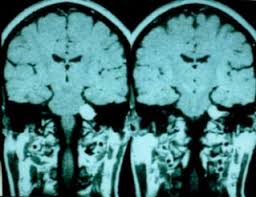

MR → Yumuşak doku detayında üstün